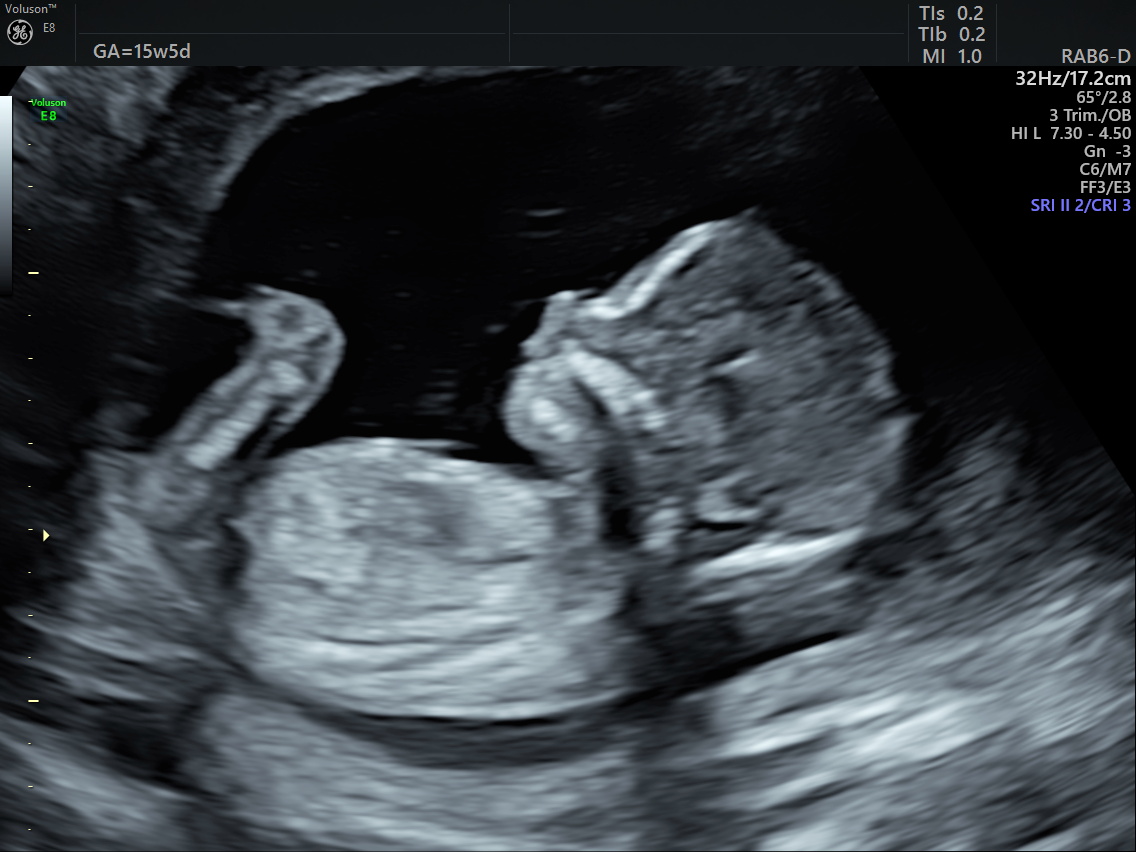

2D Scan

During the anomaly scan a detailed anatomical check is performed. Measurements are also taken to check the baby’s growth.

A professional Sonographer will show you the baby the in detail, such as:

- Head,

- face,

- chest,

- heart,

- stomach,

- kidneys,

- bladder,

- cord insertion,

- spine,

- upper and lower limbs,

- the position of the placenta and

- if there is a normal amount of fluid around the baby.